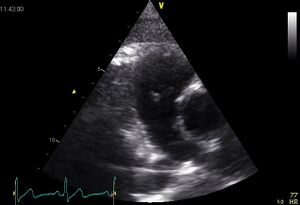

| Plax by tilted (Plax PV) | PSax Ao |

| Suprasternal apd (color doppler) | Dilated apd (Plax PV) |